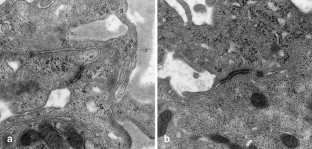

A chordoid glioma in the third ventricle was studied immunohistochemically and ultrastructurally. In this report, special attention is paid to the histogenesis in relation to the pathological appearance and unique anatomic location of this tumor. Light microscopic and immunohistochemical findings were similar to those reported previously. Ultrastructurally, microvilli were frequently seen, but three types of abnormal cilia were rarely observed. Basement membrane around the tumor cells and microvessels was extensive. Poorly to moderately developed intermediate (adherent) junctions were frequently seen. Resemblance of these ultrastructural features of the tumor to embryonic tanycytes suggests the tanycytic differentiation of chordoid glioma. Neuroradiologically, all of the previously reported cases of chordoid gliomas seem to arise in the anterior part of the third ventricular floor. This region includes the lamina terminalis, infundibular recess and median eminence, which corresponds to a tanycyte-rich area. These findings suggest a tanycytic origin of chordoid glioma.

Fig. 5.